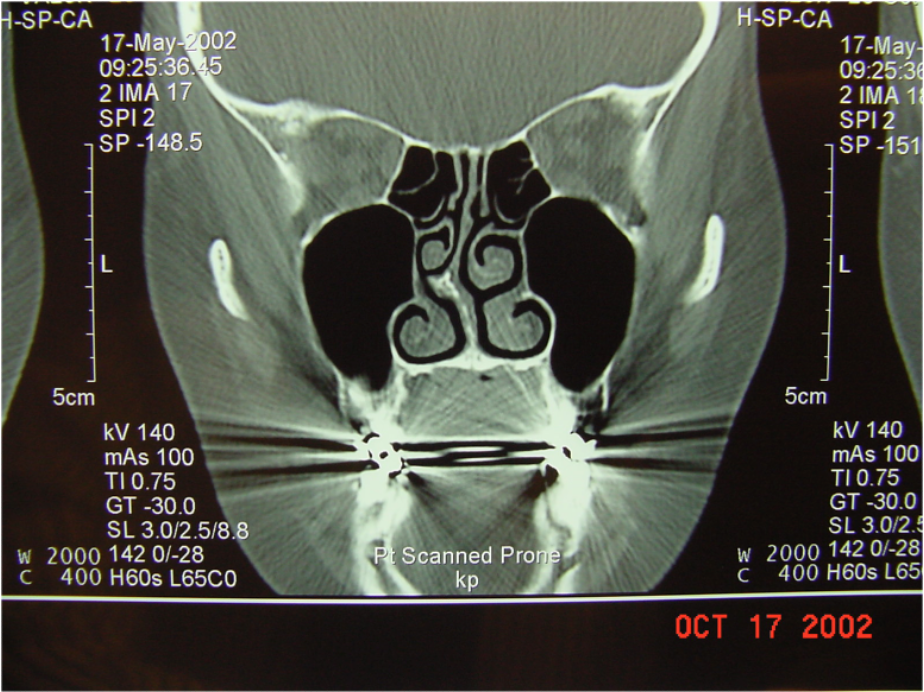

Imaging Study

- Structural abnormality.

- Suppurative complications.

Clinicians should obtain a contrast-enhanced CT scan

of the paranasal sinuses and/or an MRI with contrast whenever a child is suspected of having orbital or CNS complications of ABS